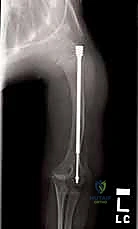

الدليل التفصيلي لخطوات العملية الجراحية: بضع العظم عبر الجلد والمسامير التلسكوبية

تُعد هذه العملية من أدق العمليات في جراحة عظام الأطفال، وتتطلب مهارة استثنائية كما هو الحال مع البروفيسور محمد هطيف. يتكون المسمار التلسكوبي (Fassier-Duval) من جزأين يتداخلان ببعضهما البعض (مثل التلسكوب). يتم تثبيت أحد الأطراف في أعلى العظم والطرف الآخر في أسفله. عندما ينمو العظم، ينزلق الجزء الداخلي من المسمار للخارج، مما يسمح للعظم بالنمو الطبيعي دون أن ينثني أو ينكسر.

بعد تقويم العظم وجعله مستقيماً كحبات المسبحة على خيط، يتم إدخال السلك الدليلي (Guide Wire). ثم يتم إدخال الجزء الخارجي (الأنثوي) من المسمار التلسكوبي وتثبيته في الجزء العلوي من العظم (Epiphysis).

بعد ذلك، يتم إدخال الجزء الداخلي (الذكري) من المسمار عبر الجزء السفلي من العظم وتثبيته في المشاشة السفلية. هذا التصميم العبقري يضمن حماية العظم بالكامل من الداخل.

المسمار العادي ذو طول ثابت، وعندما ينمو عظم الطفل، يصبح المسمار قصيراً ولا يحمي الأطراف الجديدة للعظم، مما يؤدي لكسرها. أما المسمار التلسكوبي فهو مصمم من قطعتين تتمددان مع نمو العظم (مثل هوائي الراديو القديم)، مما يوفر حماية دائمة للعظم طوال فترة النمو.